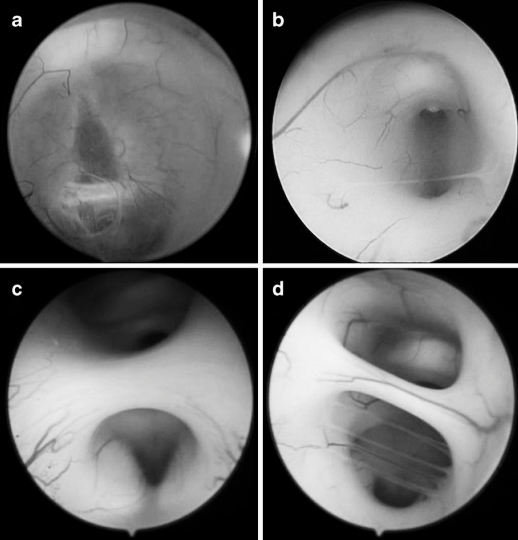

图5 内镜下第三脑室底的不同表现,导致实施 ETV(内镜第三脑室造瘘术)难度递增:a 呈水平状、半透明且菲薄,可清晰辨认漏斗隐窝;b 呈实质样,伴细薄下丘脑粘连;c 呈实质样,伴肥厚下丘脑粘连;d 呈实质样,伴肥厚下丘脑粘连及多条血管。

图6 第三脑室底造瘘后的内镜解剖所见。a 多层膜结构;b 实质样脑室底下方为通畅的脑池间隙;c 实质样脑室底下方存在多条蛛网膜粘连带;d 脑池深处仅见单一蛛网膜膜片,与实质样脑室底距离极远。